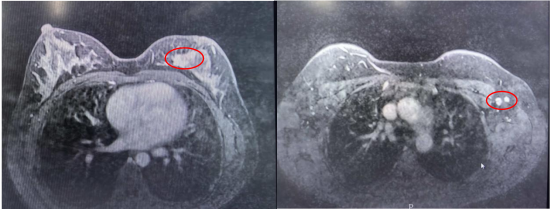

2023年10月18日 乳腺磁共振

左乳内侧缘不规则团块状异常强化信号影 BI-RADS 6类

图2 磁共振所示左乳病灶及左腋下淋巴结